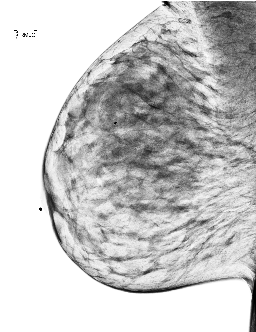

To overcome these challenges, this paper introduces MAMmography ensemBle mOdel (MAMBO), a novel approach that leverages an ensemble of diffusion models to generate mammography images at their native resolution. MAMBO uses a patch-based approach for generation which is conditioned both on local and global (full-image) context. In a nutshell, MAMBO involves the development of three distinct models: the first generates “standard”-resolution ( pixels) images to provide global context; the second increases the resolution to create local context for the target patch; and the third combines the outputs of both models to guide the generation of high-resolution patches, which are then reconstructed into a full-resolution synthetic mammogram. An example of a synthetic image generated by MAMBO is shown in Fig. 1. The image presents details at multiple resolutions, corresponding to the global and local contexts, and individual patch at full resolution. To the best of our knowledge, this is the first work to propose a diffusion model approach for generating very high-resolution synthetic mammograms.

4.1.3 Qualitative Results

The baseline for this task is a single-channel U-Net-based DDPM trained on full-resolution -pixel patches extracted from mammograms. This model learns patch characteristics but performs poorly in image reconstruction tasks. Even if the patch is not generated from pure noise but from the partially noisy patch of an original image, the reconstruction is poor, as shown in Fig. 3(c).

What MAMBO can achieve in terms of qualitative results is presented in Fig. 1 and Fig. 3(d). MAMBO is able to generate high-quality images that are visually indistinguishable from the originals, representing plausible mammogram data to layman eyes. Results are also validated with expert radiologists, with quantitative results shown in Sec. 4.2.

Fig. 3(d) illustrates what MAMBO can achieve in terms of whole mammogram generation. When using global and local context data extracted from an original image, the denoised image (Fig. 3(b)) is difficult to distinguish from the original (shown in Fig. 3(a)). When providing only the original global context and generating local context and target patches from noise, we still observe good results, as we show in Fig. 3(d).